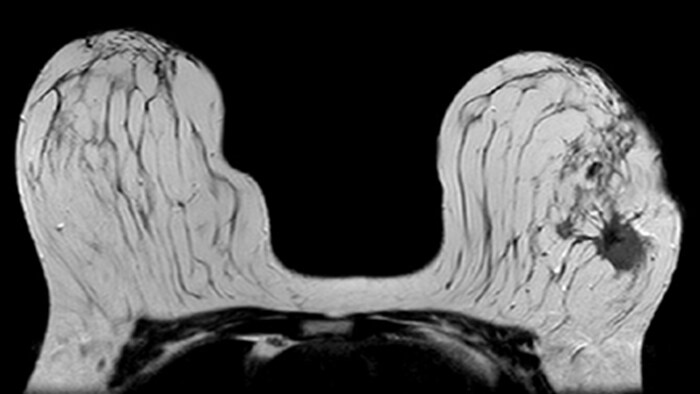

In this patient, biopsy revealed invasive ductal carcinoma in the left breast (BIRADS VI). The MRI results are compatible with multifocal multicentric malignancy in the left breast, located in the upper-inner and outer quadrants, almost from the 10 to 4 o’clock position, with an extensive intraductal component, without infiltration of the underlying pectoral muscles.